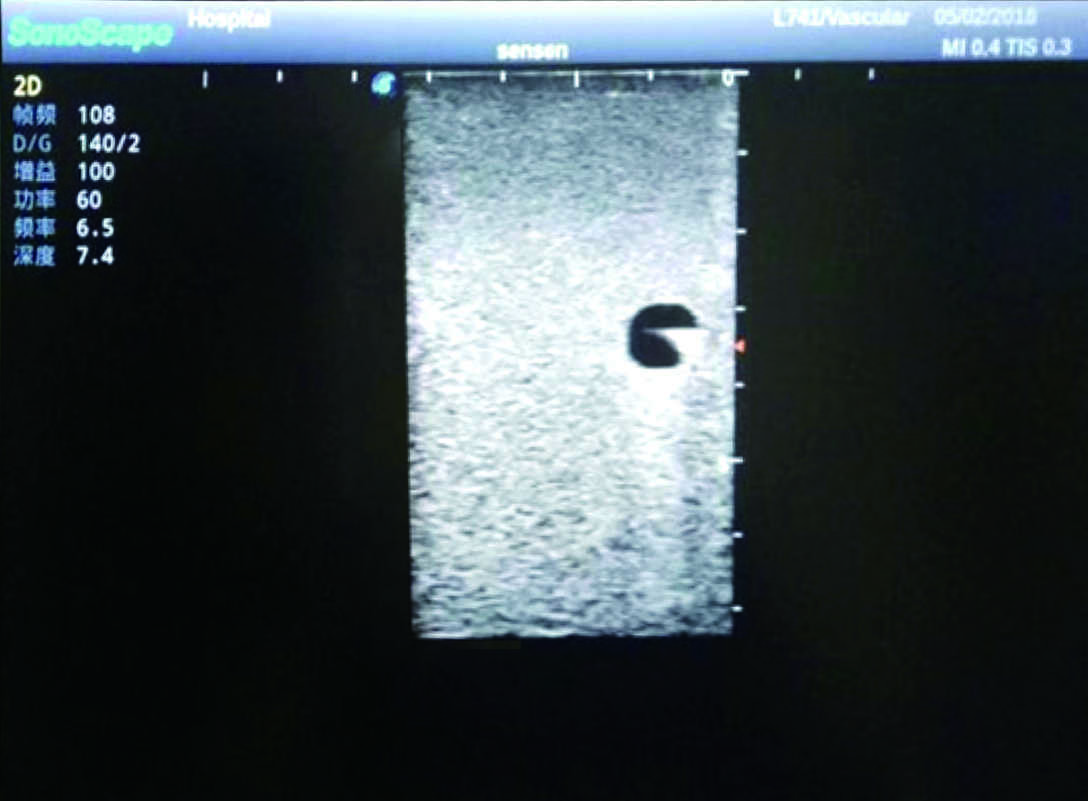

PICC Ultrasound Training Model

Model TYE1510.1

Outline

It is a model covering up from lobulus auriculae plane to the umbilical plane, and it has anatomical structures like clavicle, rib, sternocleidomastoid, jugular vein and basilic vein.

1)   Made of high molecular polymer ultrasound material, close to the real skin

2)   It can be used by real ultrasound machines

3)   Clear and real images of the tissues and organs (basilic vein and superior vena cava)

4)   When conducting vascular puncture, the piercing can be truly felt, and venous blood outflow can be seen

5)   Observe the guide wire marches

6)   Detect whether the catheter is properly placed